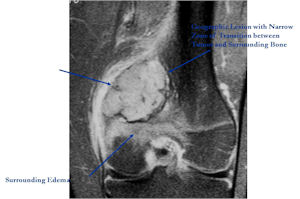

MRI:

- Also useful in determining extent

- There is often extensive edema around the tumor in the surrounding bone and soft tissues that can lead to a misdiagnosis of a malignant tumor.

- Geographic, circumscribed lesion usually around 5cm in size.

- There may be expansion of bone, cortical thinning and cortical breakthrough. A soft tissue mass may accompany this lesion but the soft tissue component is usually contained by the periosteum.

- The periosteum remains intact around the soft tissue component. Might need a CT scan to detect the subtle calcification (Egg Shell Rim of Calcification) associated with an intact periosteal reaction

- The lesion may be entirely radiolucent but usually shows some degree of mineralization. Mineralization may appear stippled like cartilage but do not see chondroid pathologically. Mineralization is sometimes better detected on a CT scan rather than an x-ray.